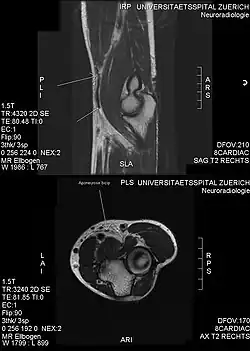

Another injury caused by bicep curls is ulnar neuropathy, which lead to ulnar nerve conduction slowing at the elbow. This is caused by compression of the nerves against a weight bench during the exercise.[22] Though unlikely, bicep curl can cause a rupture of the pectoralis major muscle, which is a severe injury that occurs in the chest.[23]